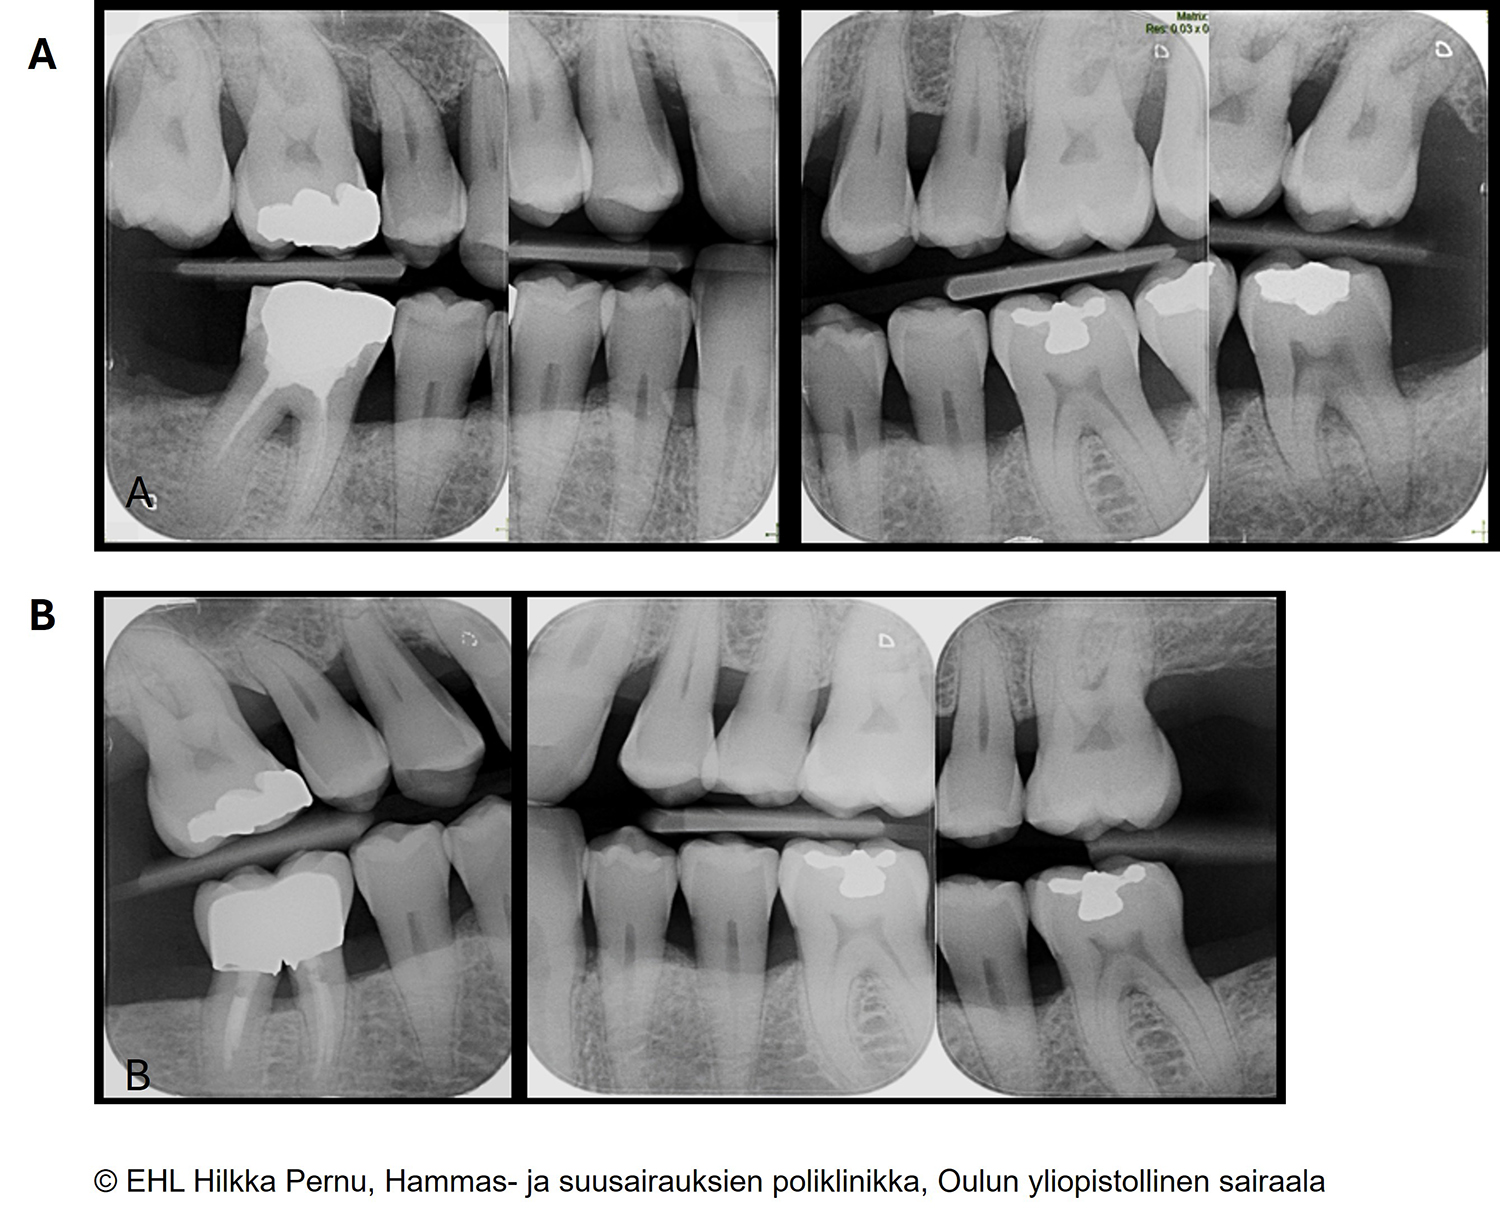

- Pystysuuntaiset bitewing-kuvat voivat olla tarpeen alveoliluukadon havainnoinnissa parodontiitin vaiheissa III ja IV «Whaites E, Drage N. Essentials at Dental Radiograp...»121, ks. kuva «Pystysuuntaiset bitewing-kuvat vaiheen III parodontiitissa»3.

Pystysuuntaiset bitewing-kuvat vaiheen III parodontiitissa.

A) Hoitoontulotilanteessa 65-vuotiaan potilaan komplisoitunut parodontiitti; pitkälle edennyt laaja-alainen luukato, vertikaalisia luutaskuja, furkaatiovaurioita ja sekundaariseen purentatraumaan viittaavia muutoksia.

B) Kokonaishoitovasteen arviointitilanteen kuvat kahden vuoden kuluttua. Marginaalinen luuraja kuvautuu tarkkarajaisena, ja alkutilanteeseen nähden luutaskuissa ja furkaatiovaurioissa on saavutettu regeneraatiota.